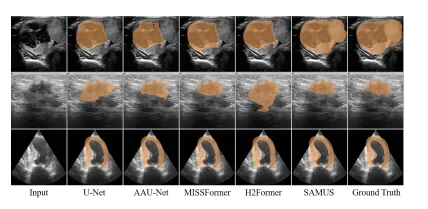

Figure 4: Qualitative comparisons between SAMUS and task-specific methods. From top to bottom are examples of segmenting thyroid nodule, breast cancer, and myocardium.

图4:SAMUS与任务特定方法之间的定性比较。从上到下分别是分割甲状腺结节、乳腺癌和心肌的示例。